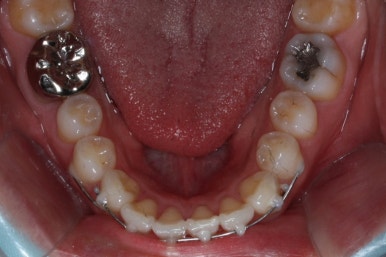

우여곡절 끝에 어찌어찌 마무리를 하게 되었습니다.

두 번째 교정에서 걸린 시간은 총 3개월이었습니다.

첫 번째 교정기간 4개월과 합하면 총 7개월이 걸렸는데 중간에 치아가 다시 삐뚤어지는 바람에 조금 많이 걸리긴 했습니다.

어쨌든, 앞니는 가지런하게 마무리가 잘 되었고, 앞니 안쪽에는 유지철사를 부착하고 치료를 종료하였습니다.

부산앞니교정 키다리아저씨치과에서 시행한 이번 MTA 부분교정의 전후 비교입니다.

위아래 앞니가 가지런해졌고, 작은 앞니의 얼룩무늬도 없어졌네요.